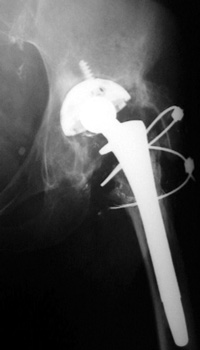

Phalanged acetabular cup with interval fracture of the medial phalange. Note progressive osteolysis in Gruen zone 7